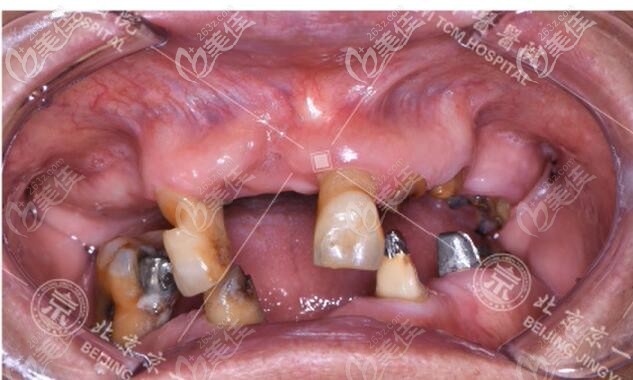

種牙前,賀爺爺?shù)目趦?nèi)情況▼

因為缺牙時間太長,賀爺爺?shù)难啦酃俏s,條件非常差,而且余牙也松動了,沒有保留價值,所以給出他的設計方案是,allon4全口即刻種植牙。